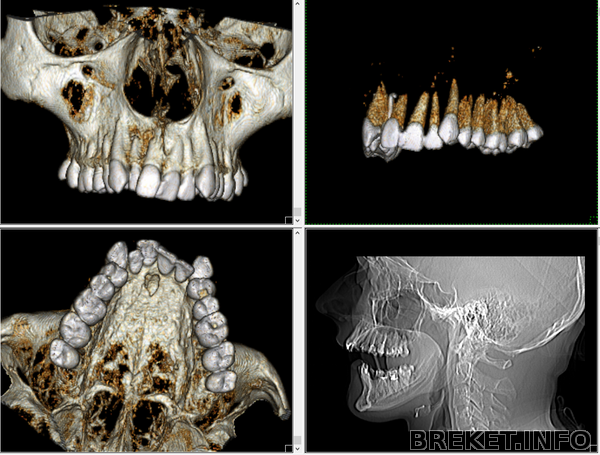

Скриншоты томографии верхней челюсти: